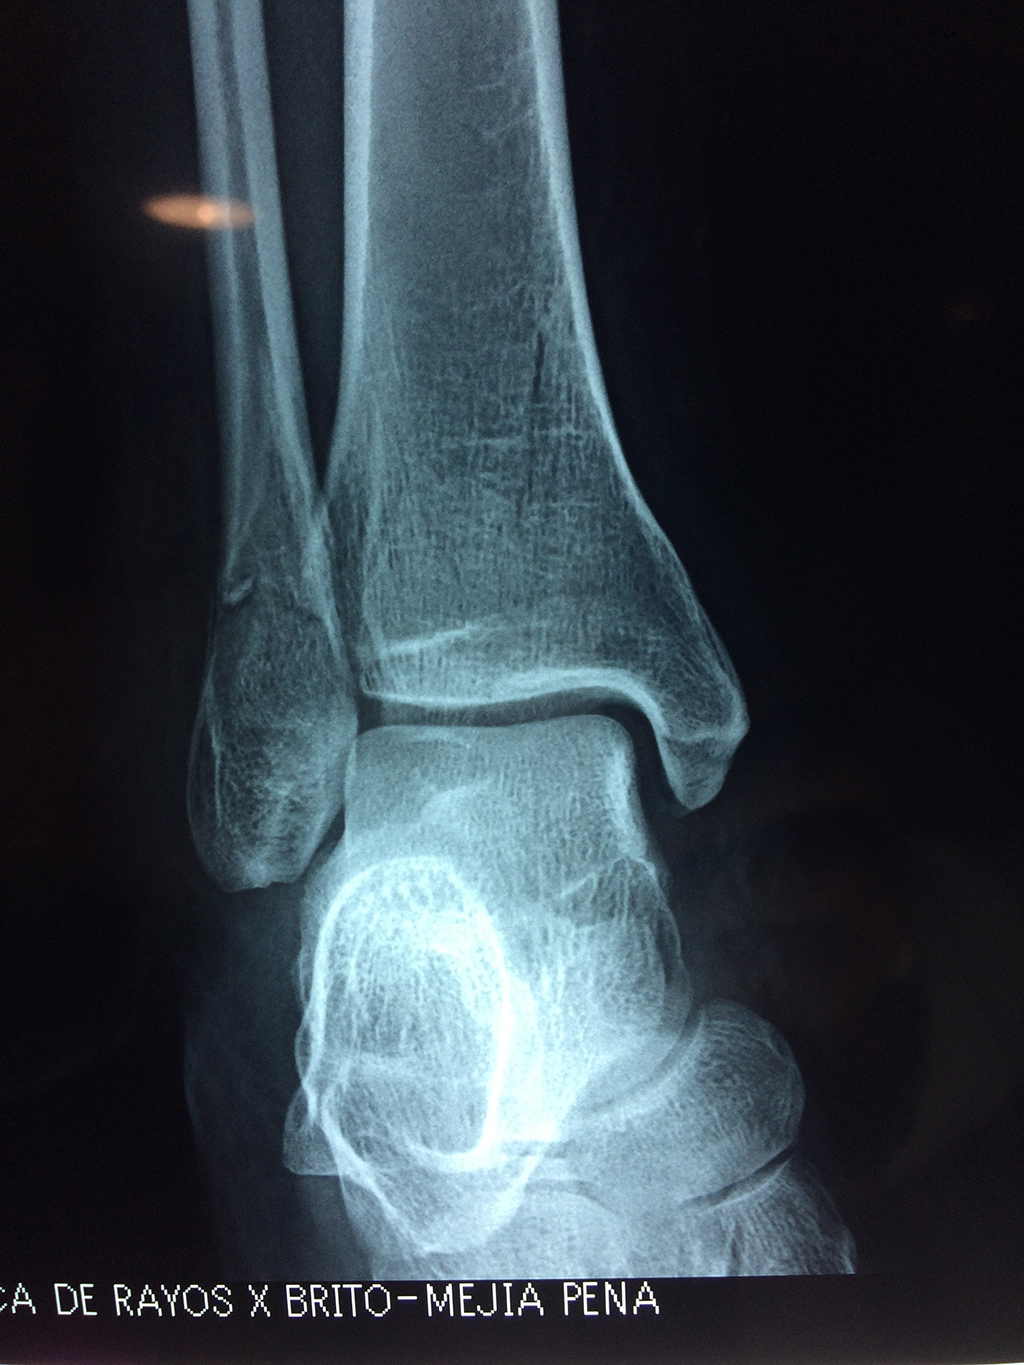

Una fractura de tobillo es la rotura de uno o más de los huesos del tobillo. Estas fracturas pueden ser:

Cuando se necesita cirugía, es probable que esta implique el uso de clavijas de metal, tornillos o placas para sostener los huesos en su lugar mientras la fractura se consolida. Los elementos de soporte pueden ser temporales o permanentes.